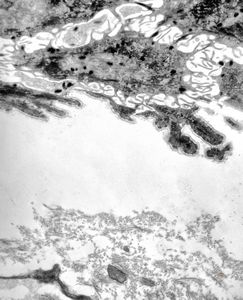

M, 22y. | epidermolysis bullosa - junctional type

M, 22y. | epidermolysis bullosa - junctional type, uncompletely separated basement membrane